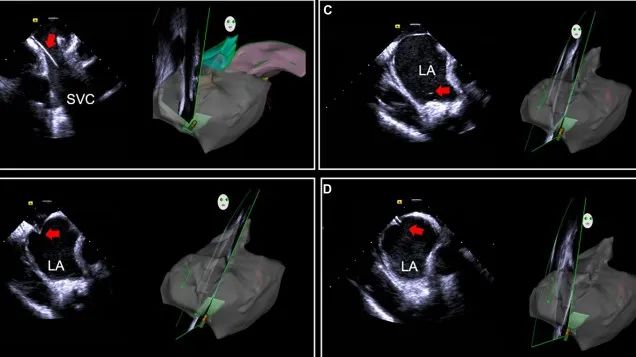

心腔內(nèi)超聲(ICE)技術(shù)壁壘極高,國內(nèi)主要廠商核心部件仍舊為進口,集成了超聲和圖像處理最前端技術(shù),包括超聲探頭、線纜、軟件成像算法等,是當前內(nèi)窺超聲方向最具挑戰(zhàn)的領(lǐng)域。ICE的應(yīng)用經(jīng)歷了2D平面成像、3D三維立體成像、以及4D的實時三維立體成像階段。